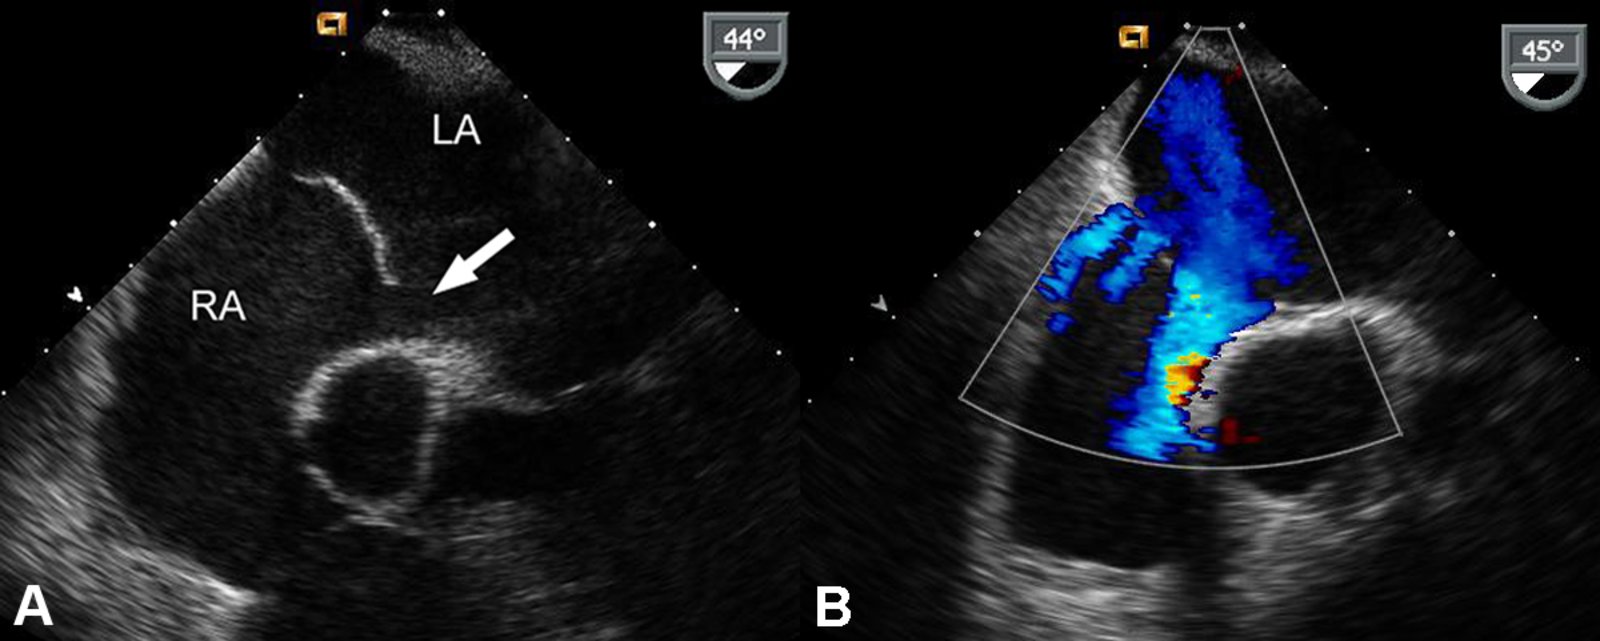

Echocardiography (confirmatory test) :

-

TTE with Doppler

- Confirms interatrial communication

- Best visualized in the apical four-chamber and subcostal views

- Agitated saline study: if TTE findings are equivocal [23]